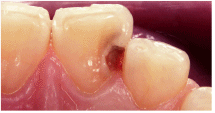

虫歯の確認 |

治療に入る前に、虫歯の場所や大きさなど鏡や写真画像を見て確認して頂きます。

隣の歯との隣接面に穴が開いて

います。